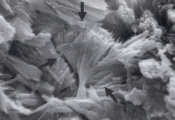

Рис. 40. Микрофотография струвитных кристаллов в мочевом осадке 2-летнего кастрированного кота (не окрашено, увеличение Х 40).

Рис. 41. Сканированная электронная микрофотография струвитных кристаллов, описанных в рис.40 (увеличение Х 1,800).